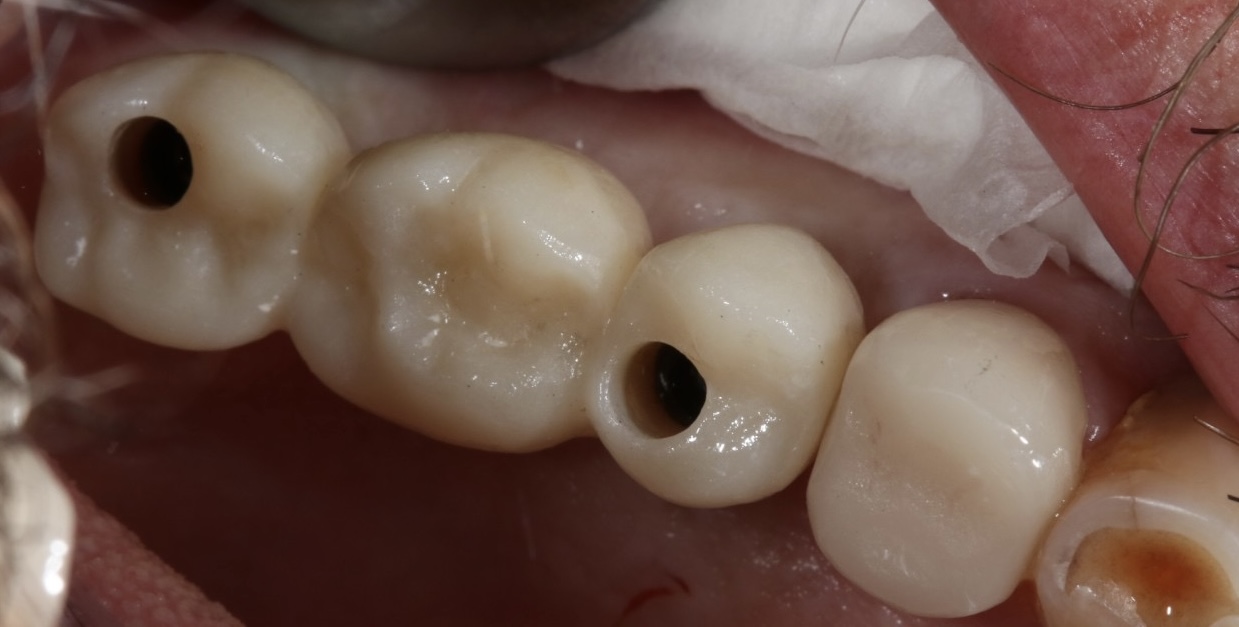

Implantati mogu da budu terapijsko rešenje u različitim situacijama - od nadoknađivanja pojedinačnih zuba u estetski najzahtevnijoj regiji kao što su prednji deo gornje vilice, preko nedostatka vićeg broja zuba pa do full mouth rekonstrukcija, gde se nadoknađuju puni zubni nizovi bilo u jednoj ili u obe vilice ALL-ON-4 ili ALL-ON-6 konceptom.

Naš tim je dovoljno iskusan i stručan za iznalaženje svih ovih rešenja pri čemu se vodimo modernim planiranjem gde željeni oblik i položaj buduće nadoknade diktira položaj implanta, što je imperativ u modernoj implantologiji.